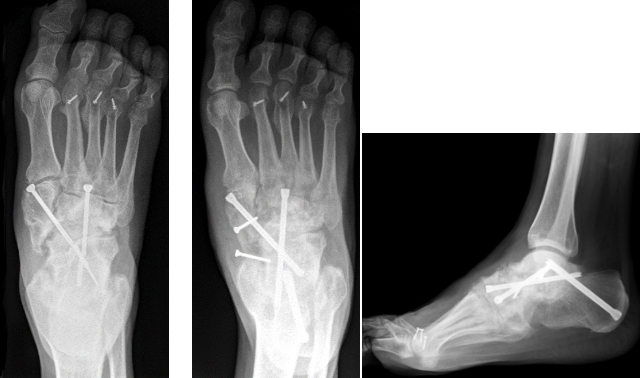

Bei voroperierten Patienten oder Patienten mit größeren Knochendefekten wie bei einer Hämophilie A (Bluter-Krankheit) sind komplexere Techniken mittels Verplattungen oder retrogradem Einbringen eines Marknagels unter Mitnahme des unteren Sprunggelenkes notwendig. Teilweise muß der knöcherne Defekt dann mittels Knocheninterponat überbrückt werden.

Versteifung des oberen und unteren Sprunggelenkes mit Knocheninterponat bei hämophilem Patienten (linke 3 Bilder) - Revision mittels retrogradem Nagel